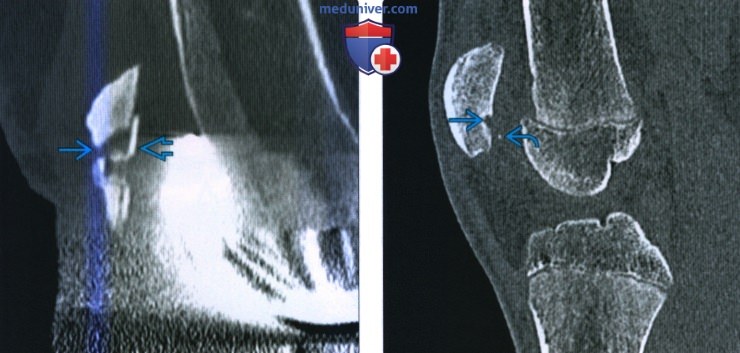

Ларсена йохансона

Ларсена йохансона 146 фото